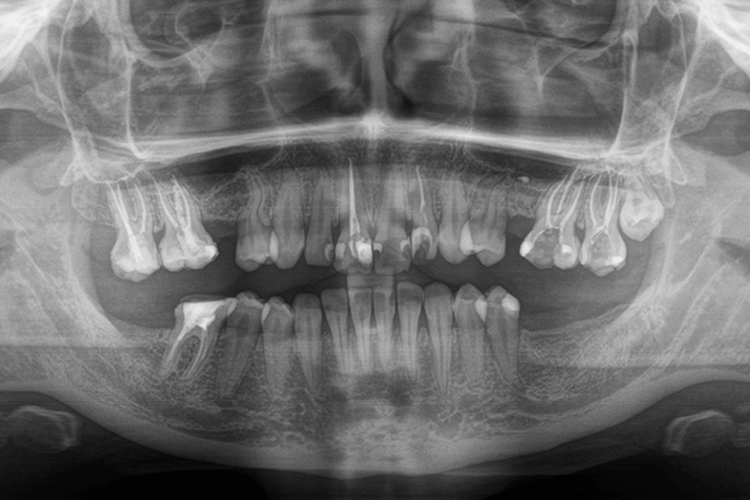

До нас в клініку звернулась пацієнтка з наступною проблемою: вторинна адентія, відсутність 5 зубів. Задача полягала не тільки у відновленні функціональності зубів, а й в покращенні усмішки в цілому.

Оскільки зуби були втрачені досить давно (2 роки тому), відбулись анатомічні зміни будови щелеп, а антагоністи відсутніх зубів висунулись вниз. Було запропоновано повернути їх в оклюзію (змикання) за допомогою брекет-системи, але термін такого лікування не влаштовував пацієнтку, тож цей план лікування далі ми не розвивали. Тоді запропонували депульпувати верхні зуби з обох боків та вкрити коронками, тобто виправити прикус ортопедичним методом.

Для відновлення відсутніх зубів нижньої щелепи запропонували встановити зубні імпланти (3 одиниці), після чого провести їх протезування керамічними коронками, а відсутні зуби верхньої щелепи відновити за допомогою мостоподібних конструкцій з опорою на сусідні зуби. Узгодили план лікування, але в процесі після установки зубних імплантів, пацієнтка звернулась до лікаря з проханням встановити зубні вініри. Нижче ми розповімо про всі етапи лікування.